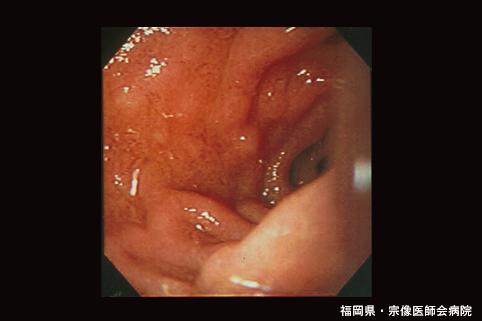

疾病(病理主体)的分类炎症性・溃疡性疾患/舍-亨二氏紫癜

部位(按器官分)十二指肠/下行脚

检查方法内窥镜